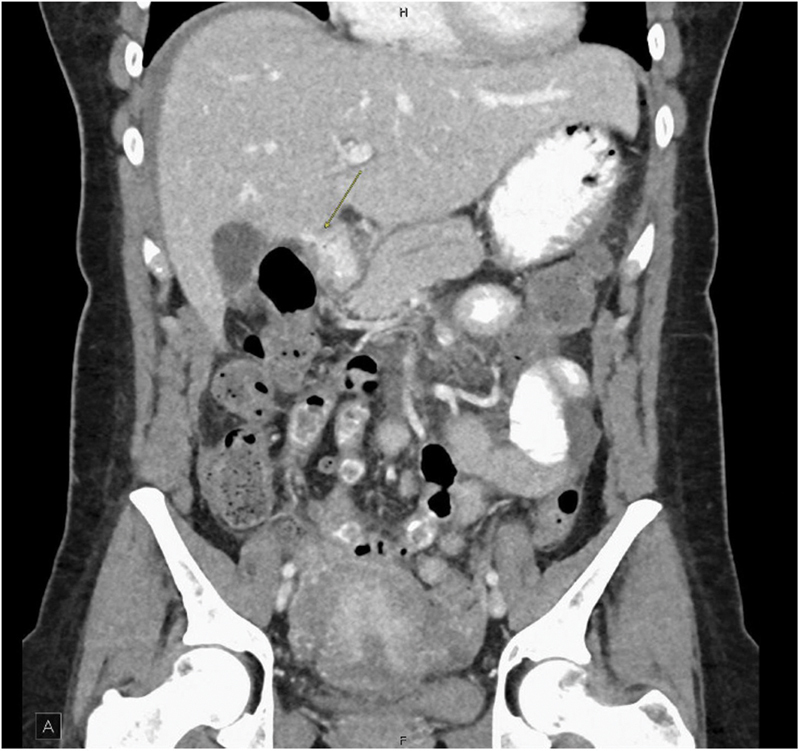

Peptic ulcers and complications, such as perforation, are rare during pregnancy and the puerperium. Accordingly, many clinicians may place these diagnoses low on their differential diagnosis. We present two case reports of primigravida, advanced maternal-age females with a history of irritable bowel syndrome and nonsteroidal anti-inflammatory drug use found to have perforated duodenal ulcers after cesarean section. Postpartum surgical abdomens may not present with classic guarding and rigidity. A low threshold for imaging and identification of risk factors is critical to timely diagnosis and management.

Abstract Image